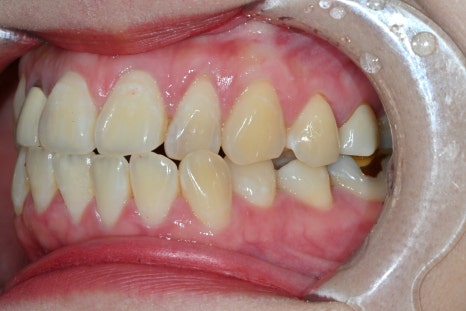

Treatment that also considers the gum line

What matters in front tooth treatment is not only the teeth but also the gums.

If the gum line looks awkward,

even the best crown

may appear unnatural.

At Seoul Of Dental Hospital,

we carry out treatment while also considering

the gum height

the gum thickness

the boundary with the tooth

In this case as well,

the final result was completed while checking the recovery state of the gums.

Naturalness completed through details

In the final stage,

we improve the quality by checking

prosthesis fit

bite adjustment

fine contact points

. Seoul Of Dental Hospital does not miss even small differences during this process.

✔ Whether it feels comfortable when chewing

✔ Whether it affects pronunciation

✔ Whether it looks natural

All of these factors are checked.